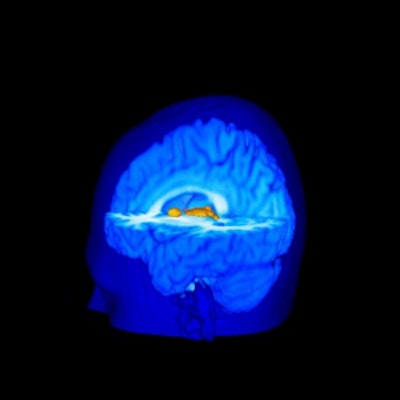

The subjects reporting greater pain from the heat stimulus also showed on MRI an increased activation of the primary somatosensory cortex (pain location and sensitivity center) and the anterior cingulate cortex (area processing the unpleasant feelings evoked by pain).

Pain-induced brain activation in highly sensitive individuals as assessed with fMRI. Note that the primary somatosensory cortex and anterior cingulate cortex had a greater magnitude of activation in sensitive individuals (above). In insensitive individuals, the thalamus displayed generally similar activation (below). Images courtesy of Robert Coghill, Ph.D.

The investigators also found insignificant MRI variations between subjects for activation of the thalamus, which participates in pain signal transmission from the spinal cord to higher brain regions.

"This difference between cortical and thalamic patterns of activation may help explain pain differences between individuals," said Coghill. "This finding raises the intriguing possibility that incoming painful information is processed by the spinal cord in a generally similar manner. But, once the brain gets involved, the experience becomes very different from one individual to the next."